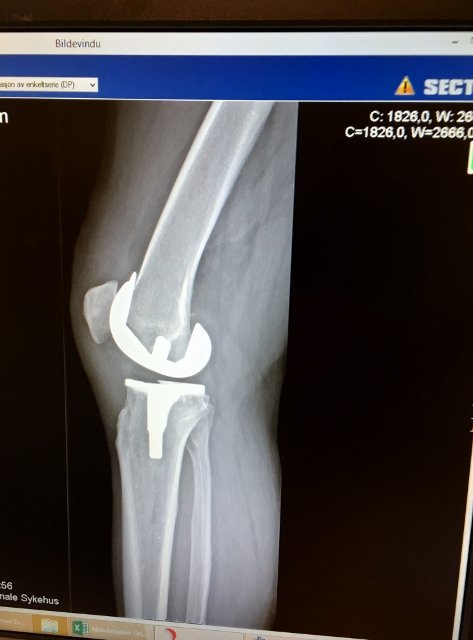

Nå har 5 måneder gått siden jeg fikk satt inn en protese i høyre kne,

og ifølge ortopeden må jeg belage meg på å ta det med ro i minst 7 måneder til,  Så drømmen om Hardangervidda lever, selv om Skrim kanskje er mer realistisk.  Riktignok prøvde jeg meg på en tur for en tid siden.  Men for å iføre meg Aktoen må jeg ned i knstående.  Det var den turen

Med tanke på Hardangervidda gikk jeg i fjor sommer fra Ustaoset til Mårbu med helprotese i høyre kne. Sekkens vekt var ved start 27 kg. Kneet fungerte og holdt. Fikk satt det inn i februar 15.

@sandressJeg ville nok heller gå på tur enn å lage ovner.  Egentlig gjør jeg dette fordi det er god smerteterapi, hvor fokus går fra smerter til noe positivt.  Dessverre er det noen av oss som sliter mye med smerter etter en kneproteseoperasjon.  Likevel, suger jeg til meg slike tilbakemeldinger som du nå har gitt.  men progresjonen går utrolig sakte.